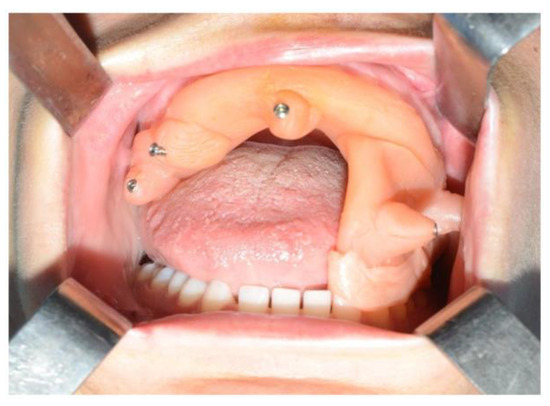

3. CASE 1: Right Coronoid Hyperplasia with Mouth Opening Deficit

A sixteen-year-old male patient exhibited dento-facial asymmetry due to hypoplasia in the right mandibular region and hyperplasia of the right coronoid. The patient had previously undergone a coronoidectomy at another facility seven years earlier, which subsequently led to restricted mouth opening (17 mm) (Figure 2a). A thick occlusal bite at maximal mouth opening was created, providing enough space for the surgical procedure and maintaining the jaw in the same position during the preoperative CT acquisition. This bite was employed to maintain the mandible in a consistent position both during the preoperative CT scan acquisition and throughout the entire surgical procedure The surgery was meticulously planned by virtually tracing the coronoid ostectomy on a CT scan. The operation was performed under general anaesthesia, utilising the navigation system. The DRF system was positioned in the left parietal region, ensuring a navigation accuracy of <0.5 mm. An incision was executed from the right inferior vestibular fornix to the right superior vestibular fornix, enabling the visualisation of the base of the coronoid process. Using surgical navigation, the sigmoid notch was precisely located, and the planned osteotomy (Figure 3) was performed in real-time, tracking the position and the direction of the periosteal elevator and piezoelectric tool (Figure 4). The piezoelectric tool and the periosteal elevator were detected by attaching the tracking tool with three reflecting spheres to the handpiece, while the tip of the piezoelectric tool and the edge of the periosteal elevator were marked and utilised as a navigation reference point. Following the procedure, the oral cavity demonstrated a notable increase in opening (36 mm) (Figure 2b).

For the subapical osteotomy, it was decided to use the tracked tool technique with a piezoelectric scalpel to perform the procedure and avoid the risk of dental root injury, thereby enhancing surgical precision. A maxillary bite was created, and 5 screws with different space vectors were then placed on it, serving as fiducial markers. The bite was used to ensure that, during the entire surgical procedure, the mandible maintained the same position as in the preoperative CT scan. Virtual planning was performed with careful consideration of dental root preservation in the osteotomy tracing. During the surgical procedure, the Dynamic Reference Frame (DRF) was positioned in the left parietal bone, and the screws located on the bite were used as fiducial markers. The same bite used during the acquisition of CT scan images was used. Two screws were secured onto the maxillary bone, with an additional one in the mandibular symphyseal region. Simultaneously, an intermaxillary fixation was used to replicate as accurately as possible the mandible’s position maintained during the CT scan image acquisition (Figure 8).

The piezoelectric tool was registered by anchoring the three reflective spheres to the tool’s handpiece. At the same time, the tip of the piezoelectric device was marked and used as a reference for navigation (Figure 9).

The navigation accuracy was less than 1 mm. The subapical osteotomy was performed as previously planned (Figure 10).

One week post-op, an OPT (Orthopantomography) X-ray was performed, which showed the adequacy of the osteotomy and the preservation of dental roots. Three years later, at the end of orthodontic alignment, the second surgical step was carried out (Figure 11a,b).